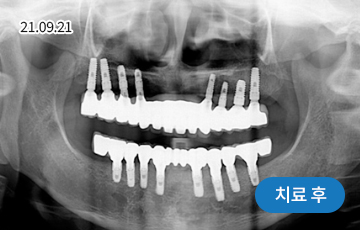

전악 임플란트

치아가 하나도 남아있지 않거나 전체적으로 상실된 경우 추천합니다.

치아의 기능을 다시 회복하기 위해 선택하는 임플란트입니다.

상실한 치아를 오랫동안 방치한 경우 상, 하악 잇몸뼈의 양도 부족한 경우가 많기 때문에 개개인의 건강 상태를 고려하여 정확한 수술 계획을 세워야 합니다.

• 치주질환으로 인해 음식을 씹기 힘들고,

미관도 좋지 않아 치아를 모두 발치한 후

전체 임플란트 수술을 하기로 결정

• 위 8개 + 아래 8개 임플란트 수술 진행 후

위 13개 + 아래 13개 (전체 치아)

임플란트 보철 제작 예정

• 임플란트 보철 완성